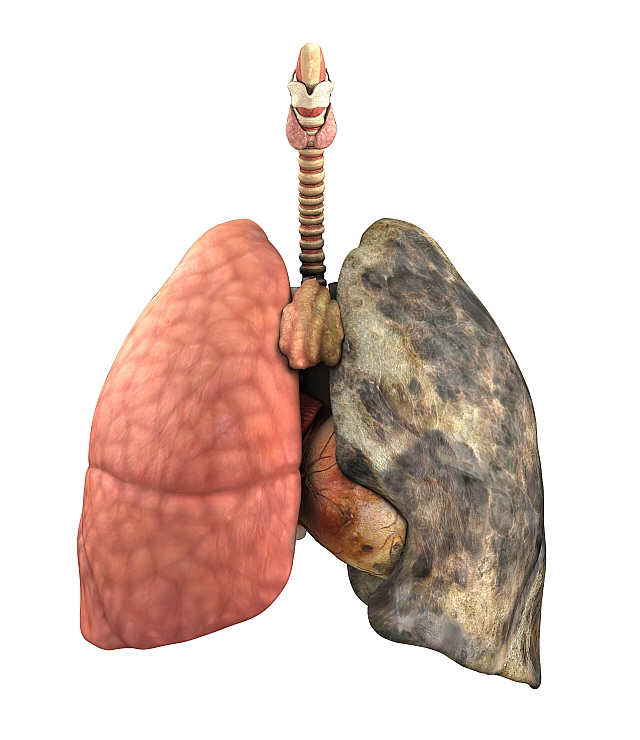

그렇다면 폐암 원인은 무엇일까요? 폐암의 가장 큰 발병 요인은 흡연입니다. 흡연자는 비 흡연자에 비해 폐암 발병확률이 15배~80배가량 높습니다.

또 다른 원인으로는 석면, 크롬 등의 물질에 노출되어 발병하거나, 대기오염과 같은 환경요인, 유전적 요인, 호흡기 질환의 과거력 등이 폐암 발병의 요인이 됩니다.

폐암을 예방하는 방법은 금연 이외에는 확실히 밝혀진 것이 없다고 합니다. 폐암의 90%는 금연으로 예방이 가능하다고 합니다.

담배를 끊은 이후에도 폐암 발병 위험의 감소 속도가 느리기 때문에 원래 담배를 안 피우던 사람보다 폐암 위험도가 20년 앞선다고 합니다.